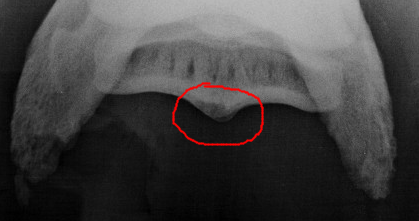

Is er ook een foto van onder af de hoef genomen? Ik heb een paard gehad met HKO, en de "standaard" röntgenfoto zag je het niet op.

Tot dat je een foto zag van de onderkant af.

Dit is de foto:

Afbeelding

Er is alleen een foto van voor- en van de zijkant gemaakt.

Oke dan kan je nog een foto van onder af laten maken.. Of MRI, dan weet je het direct maar dat is prijzig.